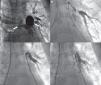

A) Angiografía del árbol pulmonar en la que se observa la tortuosidad de la rama pulmonar derecha (RPD), la gran dilatación de la rama pulmonar izquierda (RPI) y las estenosis filiformes (flechas) de 2 arterias segmentarias del pulmón izquierdo. B) Estenosis filiforme de una arteria segmentaria del lóbulo inferior izquierdo. C) La misma arteria segmentaria tras el implante de un stent. D) Angiografía tras el implante de 3 stents en la arteria lobar inferior izquierda y 2 arterias segmentarias.

A los 13 años de edad, se realizó un nuevo cateterismo cardíaco, en el que se implantaron 3 stents en la rama lobar inferior izquierda y en 2 segmentarias de esta (fig. 2). Aunque el procedimiento cursó sin incidencias, el paciente inició de forma inmediata, en la sala de hemodinámica, un cuadro de dificultad respiratoria grave, con emisión por la boca de una gran cantidad de secreción rosada que precisó intubación y traslado urgente a la Unidad de Cuidados Intensivos Pediátricos (UCIP). En las horas siguientes, el paciente presentó un deterioro progresivo, con edema pulmonar masivo con opacificación pulmonar bilateral y signos ecocardiográficos de presión suprasistémica del VD. Ante la ausencia de respuesta a la ventilación con PEEP alta y la administración de óxido nítrico inhalado, junto con hipotensión arterial refractaria a la administración de volumen y perfusión de fármacos vasoactivos, se decidió su canulación y asistencia con oxigenación por membrana extracorpórea (ECMO).